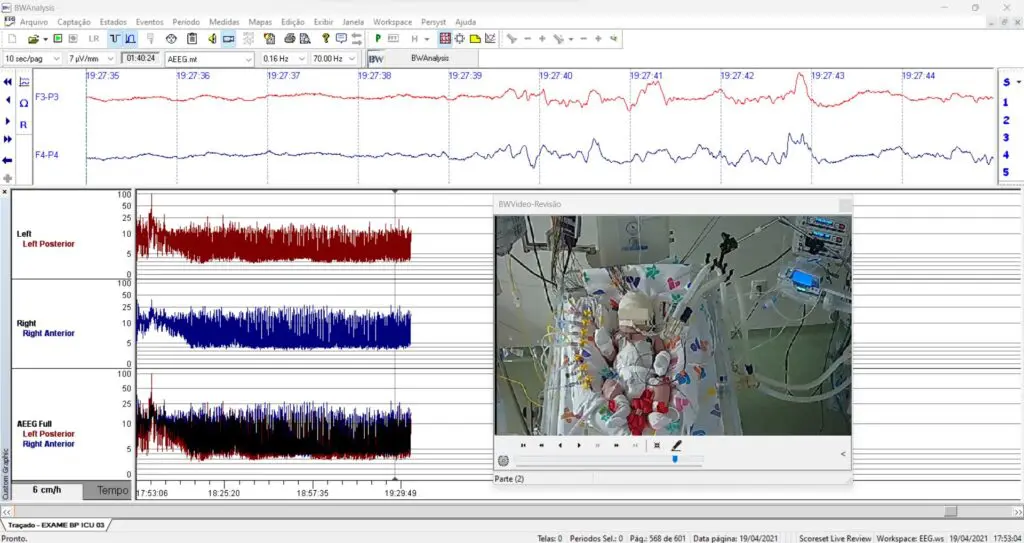

eeg 2008年 Neurovirtual / Sleepvirtual O Eletroencefalograma em Neonatosの詳細情報

Neurovirtual / Sleepvirtual O Eletroencefalograma em Neonatos。Neurovirtual / Sleepvirtual O Eletroencefalograma em Neonatos。Tênis ZX750 Bege - Adidas - Tênis Esportivo - Magazine Luiza。eeg2008年5.6.7.8.9.10.11.12月号折り目が結構あります。シャネルSUPER COLLECTION 2005 レア雑誌。⚠️古い雑誌なのでご理解の上購入お願い致します。EEG mostra foco temporal esquerdo, em montagem com Cz. | Download。9月号は写真の通りです。⚠️雑誌の状態はよくありません。スーパー戦隊 オフィシャルムック 20世紀 21世紀 42冊セット。ZOIDS ゾイド バトルコミック。